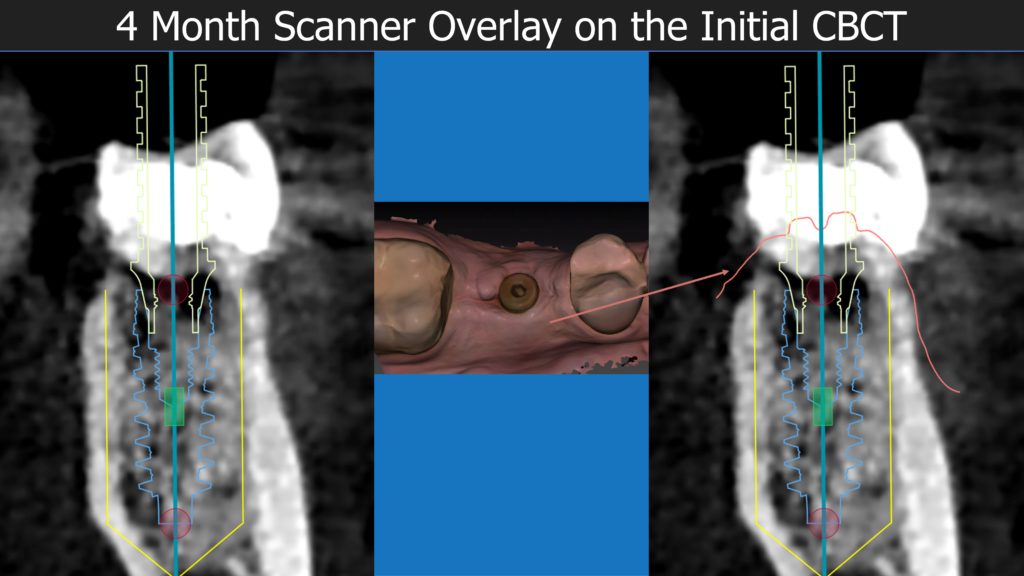

A healthy 36 year old woman comes to the clinic with pain and swelling in the area of the inferior left molars. In the intraoral observation, a vestibular fistula was identified, and the complementary exams confirmed a bone lesion caused by a root perforation (poorly executed false post) on the first lower left molar #36 (19). It was decided to do antibiotic therapy for a week and then the tooth extraction with immediate implant placement and bone graft. 4 months post-op the definitive zirconia/ceramic crown would be was made.